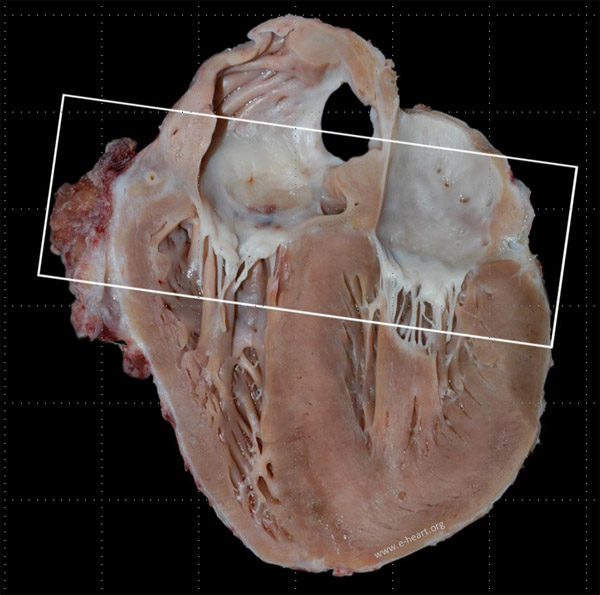

Allograft vasculopathy involves both epicardial and intramural coronary arteries. The classic feature of CAV is that of diffuse concentric narrowing with luminal stenosis. The images below show gross examination examples of allograft vasculopathy in a pediatric age heart. The epicardial coronaries are markedly thickened. Microscopic features of allograft vasculopathy are shown here.

This coronal four chamber view of the heart shows the circumflex and the right coronary arteries. Close up of the area framed by the rectangle.